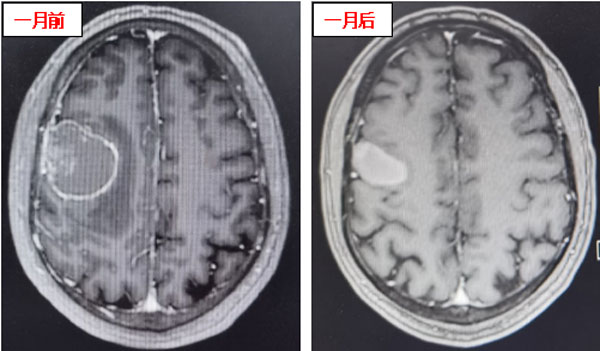

患者在接受3次射波刀治療后,頭痛癥狀明顯減輕,癲癇癥狀消失,肢體肌力明顯好轉。接受治療1個月后,患者肢體肌力恢復正常,未再出現口角、肢體抽搐及頭痛、頭暈等癥狀,僅左側手指尖偶有麻木感。復查頭顱核磁顯示:顱內病灶明顯縮小,周圍無明顯水腫壞死征象,安全性良好,這意味著射波刀治療成功遏制了顱內轉移瘤。